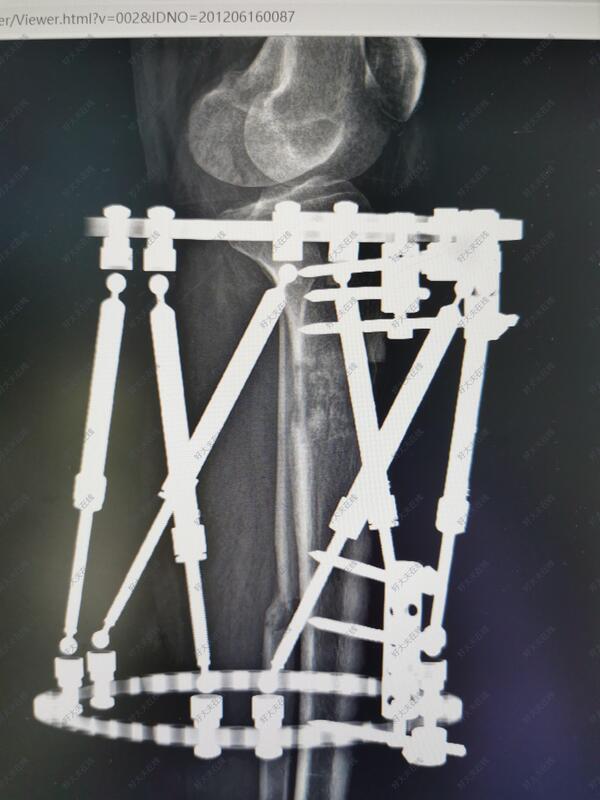

治疗后

- 治疗后90天

术后2月可以去上班,现在拆除部分外固定针实现动力化